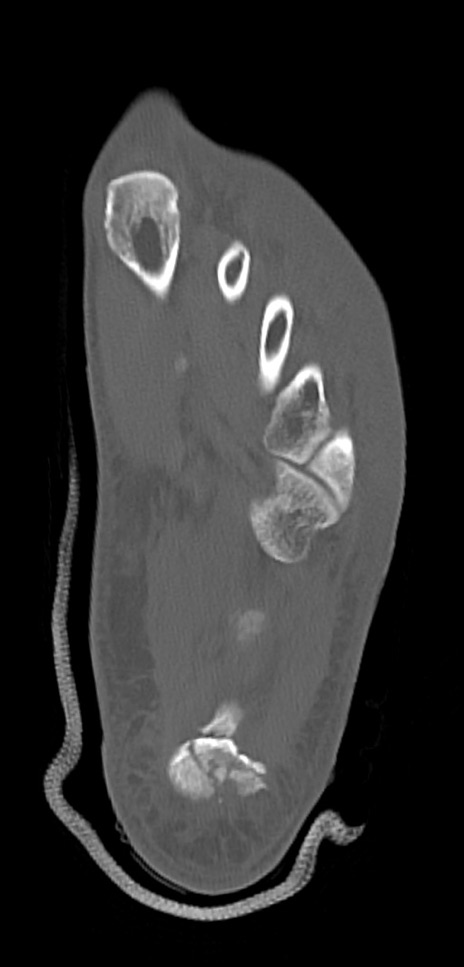

症例37 左足関節CT(横断像)

左足関節CT

冠状断像